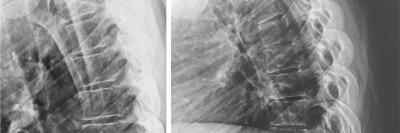

Makromastie – mehr als nur ein ästhetisches Problem

Chronische Schmerzen, Wirbelsäulenbeschwerden und neurologische Symptome belasten viele Frauen mit Makromastie. Die Brustverkleinerung kann helfen, doch die Kostenübernahme bleibt oft ein Hindernis. Gleichzeitig fehlt es an abgestimmten Behandlungsstrategien. Ein Appell an die interdisziplinäre Behandlung.

Bildnachweise